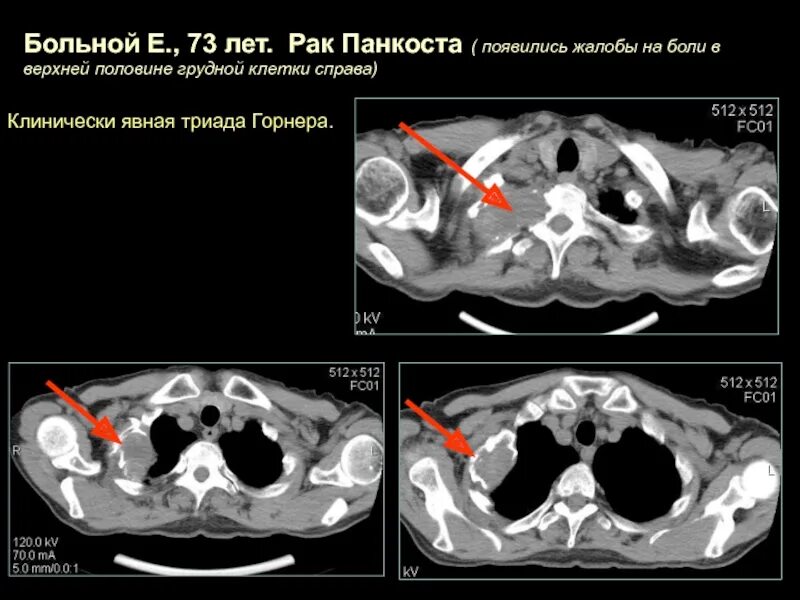

Что такое кт при онкологии